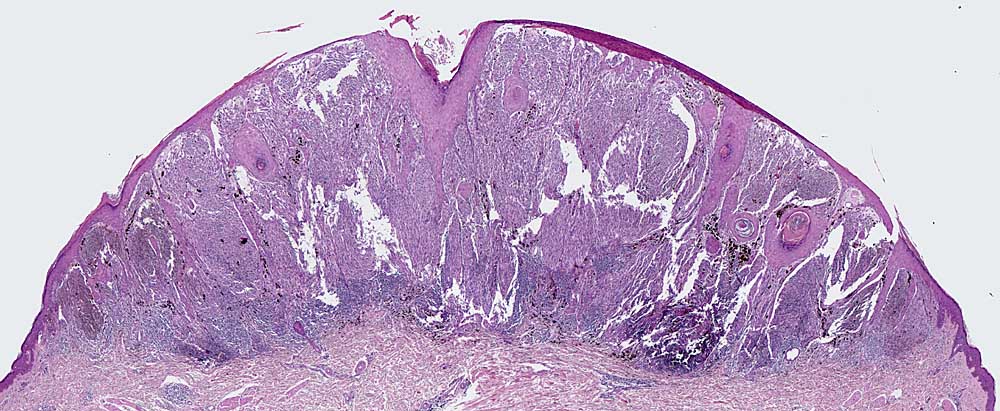

PathoPic – image database / PathoPic ID 6720 - spitzoides Melanom

spitzoides Melanom

maligner Tumor

Haut, Kopf

Haut

Nachweis zahlreicher Mitosen

Histologie

25